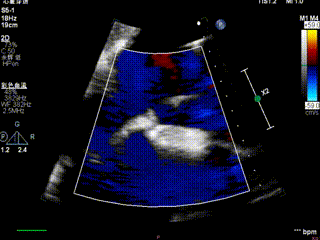

送入第二枚SW0609(短宽型)二尖瓣夹,使其紧贴第一枚夹子。在食道心脏超声三维多平面重建(3D-MPR)引导下,将夹子跨瓣送入左心室。首次尝试捕捞并夹持瓣叶后关闭夹子,外侧反流量仍较多;随后反转夹子并重新捕捞夹持成功,此时前后叶活动均受限,外侧反流显著减少。释放夹子后,三维超声显示组织桥稳定,反流减轻至轻中度,平均跨瓣压差未见狭窄征象,肺静脉逆流亦有所改善。

第二枚夹子释放后血流

怎么上穿刺鞘攻克巨大左房伴转位穿刺难关!温医大附一院周浩教授团队创新应用“导丝定位+可调弯鞘”技术完成高难度TEER手术_https://www.jmylbn.com_新闻资讯_第35张

第二枚夹子释放后组织桥稳定

第二枚夹子释放后血流3D

第2枚夹子释放后压差